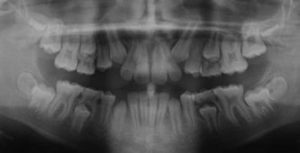

Impacted Canines